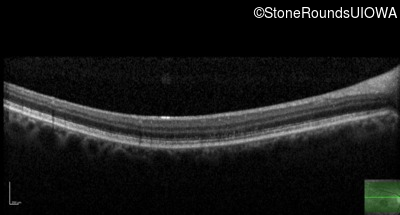

AR Stargardt Disease (IIA)

Age at visit: 54 years

This 54 year old woman first noticed reduced visual acuity in her mid 20's.

Diagnosis & molecular findings

Disease Gene Allele 1 variant(s) Allele 2 variant(s) Inheritance mode

AR Stargardt Disease ABCA4 Gly1961Glu GGA>GAA Cys2150Tyr TGT>TAT AR